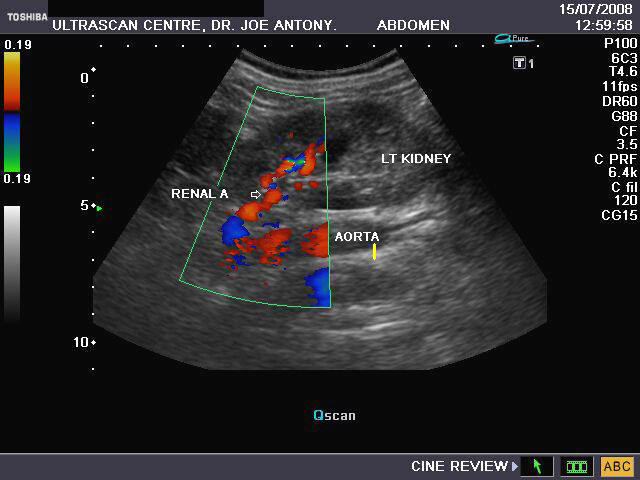

It takes patience and favourable imaging conditions (like thin abdominal wall and patient cooperation) to locate the renal arteries and veins by color doppler and even more difficult to get a spectral waveform tracing of the vessels. The upper few color doppler images show the left renal artery as it emerges from the abdominal aorta and enters the renal hilum. The lower few images show the right renal artery and right renal vein. Spectral tracing shows typical normal arterial and venous flow patterns. Ultrasound and color doppler images taken using a Toshiba Nemio XG color doppler machine by Joe Antony, MD, Cochin, India.